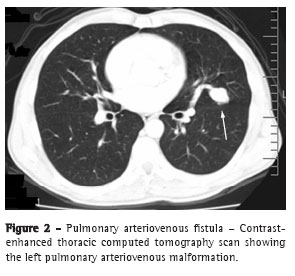

A 49-year-old man presented for medical treatment with a 30-year history of recurrent epistaxis, which had become less frequent in the last years. He also reported progressive fatigue and pallor over the last decade, together with progressive dyspnea, exacerbation of fatigue, pallor and weight loss of 6 kg over the preceding six months, as well as a family history of telangiectasias. He had no addictions and presented no hemoptysis or chest pain. In the physical examination, discolored mucosa, pallor, blood pressure of 110/70 mmHg and a 2/6 systolic ejection murmur were observed, together with telangiectasias in the oral mucosa, lips (Figure 1) and palate. The chest was clear to auscultation, and there was no digital clubbing. The blood workup performed at admission revealed the following: iron deficiency anemia with hemoglobin of 3.8 g/dL; mean corpuscular volume: 58.5 fL; red cell size distribution: 32.6%; and ferritin: 3.5 ng/mL. The results of red cell, folate and vitamin B12 tests, as well as those of a clotting screen, were normal. The test for occult blood in feces was positive. The chest X-ray showed a well-circumscribed nodule of 1.5 cm in diameter in the right lower lung lobe and a 1-cm nodule in the left middle lobe. These findings were consistent with pulmonary AVMs, which were confirmed through contrast-enhanced computed tomography scans of the chest (Figure 2). During complementary evaluation, endoscopy of the upper digestive tract indicated multiple gastric angiodysplasias (Figure 3). Echocardiography with agitated saline contrast medium was used to detect intracardiac or intrathoracic shunts. The echocardiogram revealed microbubbles in the left atrium within three cardiac cycles of their appearance in the right atrium, indicating intrapulmonary shunting. Cranial angiotomography, abdominal ultrasound and colonoscopy results were normal. A diagnosis of HHT was established. Two weeks of blood transfusions and iron therapy improved the anemia significantly, raising hemoglobin to 10 g/dL. After three months of outpatient evaluation, the patient remained symptom free.